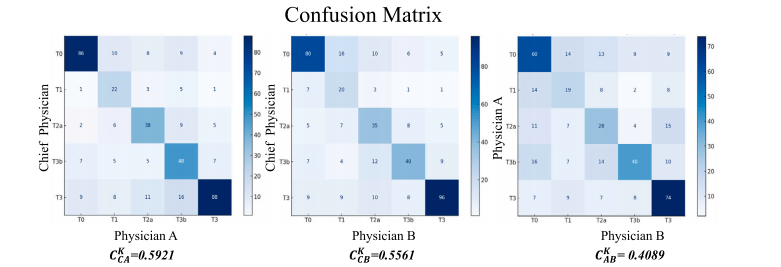

Fig. 11. Annotation confusion matrix and kappa coefficient within the annotation committee. 𝐶**𝐶 𝐾 𝐴 represents the kappa coefficient between C and A, and so forth

图11:注释委员会内部的注释混淆矩阵和卡帕系数。𝐶𝐶 𝐾 𝐴表示C和A之间的卡帕系数,以此类推。